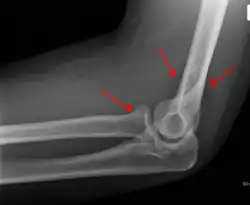

Fat pad sign: Ventral fat pad bowed and dorsal fat pad visible in a case of a nondisplaced fracture of the radius head which is not visible directly.